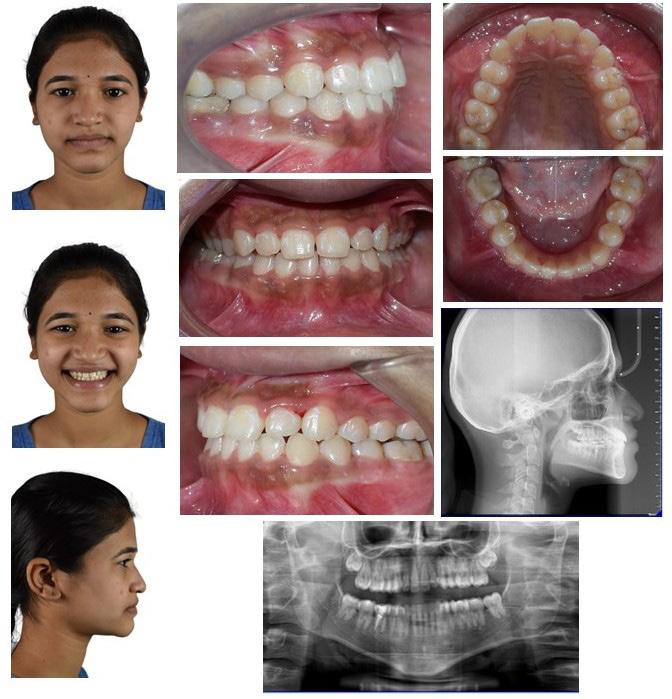

Standard orthodontic pretreatment records (T0) were obtained (Figure 1). The same operator obtained the lateral cephalogram and OPG using the same machine. The lateral cephalograms were traced manually with the standard technique by a single

Figure 1:Pre-treatment Orthodontic records